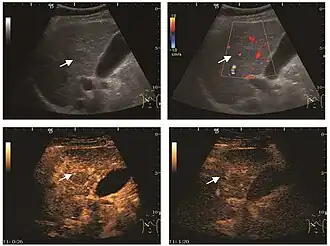

The ultrasound appearance is a well defined lesion, with very thin, almost unapparent walls, without circulatory signal at Doppler or CEUS investigation. The content is transonic suggesting fluid composition. The presence of membranes, abundant sediment or cysts inside is suggestive for parasitic, hydatid nature. Posterior from the lesion the acoustic enhancement phenomenon is seen, which strengthens the suspicion of fluid mass. They typically displace normal liver vessels but no vascular or biliary invasion occurs.

Liver cyst

Hydatid liver cyst. Diagnostic criteria are the presence of membranes and sediment inside.